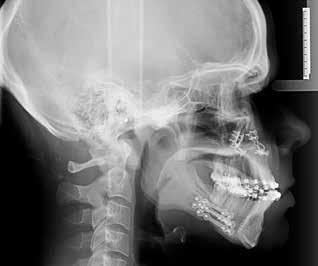

SAGBAKKEN P, KJELLERUP AD, STARCH-JENSEN T

Mandibulær midtlinjedistraktionsosteogenese til korrektion af transversel okklusionsafvigelse / 590

I den næste artikel vender vi os mod ortodontiskkirurgisk behandling. Emnet er transversel udvidelse af mandiblen ved midtlinjedistraktionsosteogenese. Dette illustreres og gennemgås i en interessant kasuistik. Vi har også her tidligere bragt artikler om distraktionsosteogenese. I 2021 såvel en oversigtsartikel om emnet som en kasuistik om unilateral mandibulær distraktionsosteogenese. I dette nummer bringes en kasuistik om en 15årig dreng med vækstbetinget kæbedeformitet med betragtelig transversel okklusionsafvigelse, der korrigeres med ortodonti og mandibulær midtlinjedistraktionsosteogenese. Behandlingen angives som forudsigelig, om end med betydelig risiko for recidiv samt diverse komplikationer. Derfor anbefales behandlingen udelukkende til ekstreme vækstbetingede transverselle okklusionsafvigelser.